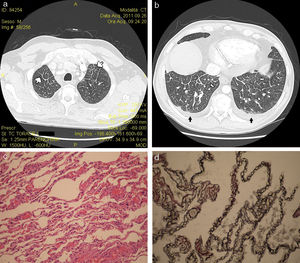

Reconstrucción volumétrica con TCAR en ventana de parénquima de los lóbulos pulmonares superior (a) e inferior (b) mostrando engrosamiento liso multifocal de los septos interlobulillares (flechas blancas) y derrame pleural bilateral leve (flechas negras). Las características histopatológicas (c) incluyeron engrosamiento marcado de los septos interlobulillares y las paredes alveolares, ocupados por una extensa proliferación de vasos sanguíneos de pared delgada y pequeñas áreas de inflamación linfocítica intersticial (tinción de hematoxilina y eosina; magnificación 30×). Las células endoteliales eran positivas a tinción con el anticuerpo monoclonal CD31 (d) (magnificación 40×).

Un exfumador de 53 años de edad (39 paquetes/año) acudió por empeoramiento de su disnea de esfuerzo de 4 años de evolución y fatiga. Al ingreso, el paciente presentaba taquipnea importante (frecuencia respiratoria de 35 respiraciones/min) secundaria a hipoxemia grave (40,5mmHg). El electrocardiograma mostró intervalo PR de 140 milisegundos, con onda P pulmonar, bloqueo de rama derecha y frecuencia cardíaca de 94lat/min. Los resultados analíticos fueron normales. No se realizó exploración completa de la función pulmonar por negativa del paciente. La espirometría reveló una alteración ventilatoria obstructiva leve no reversible con broncodilatadores. En la radiografía simple de tórax se observó congestión hiliar no específica (no se muestra) y el ecocardiograma mostró hipocinesia grave del ventrículo derecho, acompañada de importante dilatación de la aurícula derecha con presión sistólica estimada de la arteria pulmonar de 70mmHg. El paciente rechazó la realización de cateterismo cardíaco derecho. Se descartó enfermedad pulmonar tromboembólica tras realización de tomografía computarizada (TC) con contraste. Los principales hallazgos radiológicos se ilustran en la figura 1, paneles a y b. Se inició tratamiento oral con carvedilol (12,5mg/día) y furosemida (125mg/día) y se dio de alta al paciente con cuidados de apoyo. Fue reingresado a los 3 meses por empeoramiento clínico y se realizaron más exploraciones. En ese momento, más del 90% de las células obtenidas por lavado broncoalveolar se teñían con azul de Prusia de Perl, indicativo de depósito de hierro, y las características de la biopsia de pulmón sugerían HCP (fig. 1c y d). El paciente fue derivado a un centro de trasplante de pulmón. Su estado clínico es todavía grave, pero estable hasta la fecha pasados 50,4 meses desde el diagnóstico.